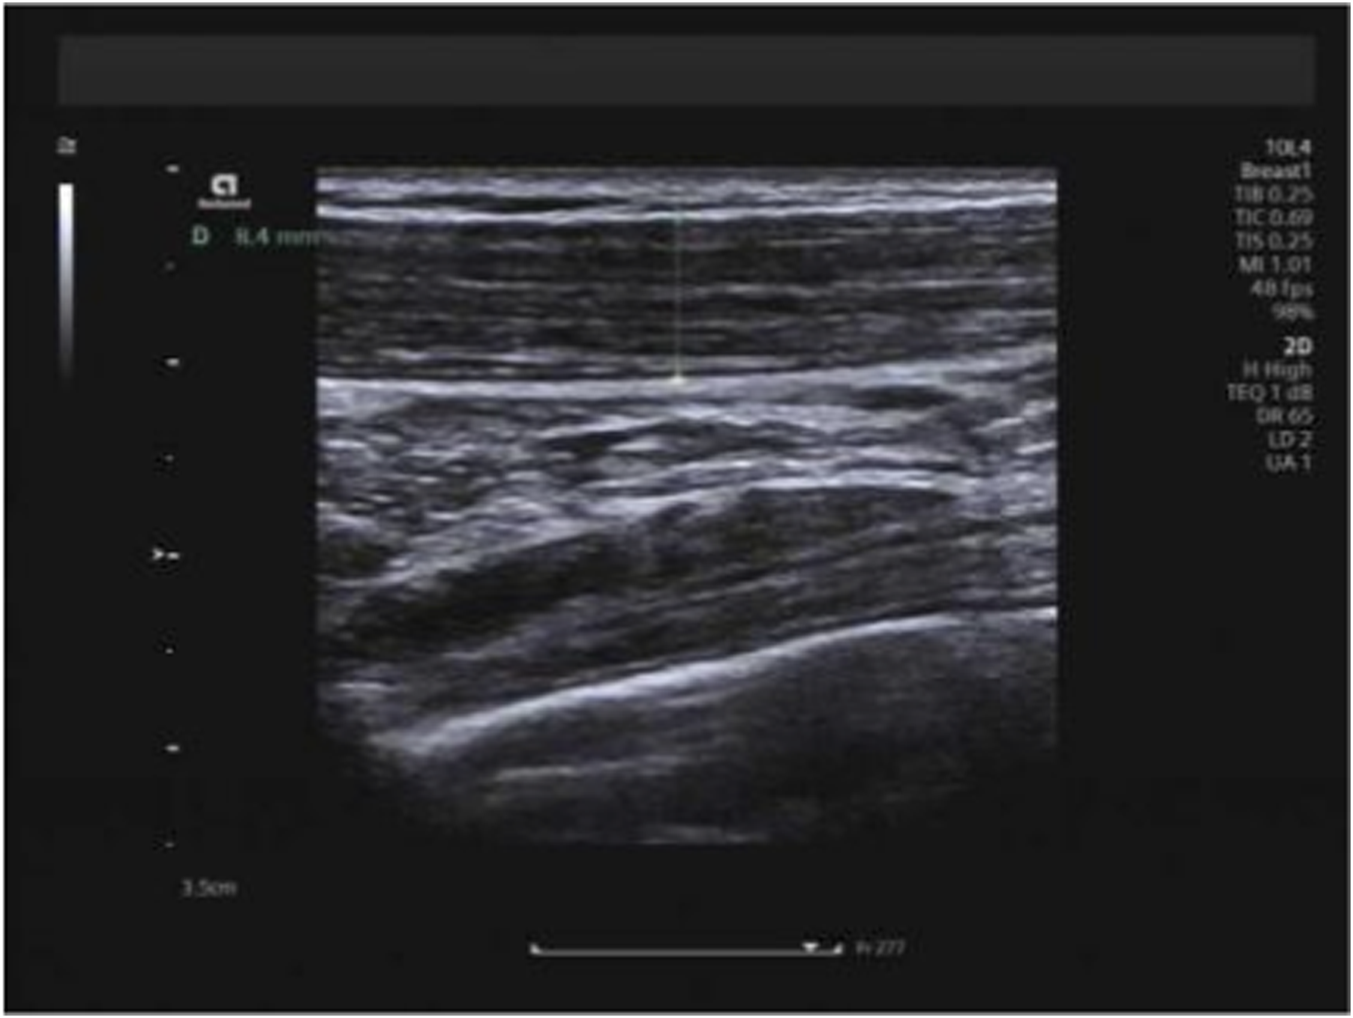

All examinations were performed using a Siemens ACUSON Redwood color Doppler ultrasound system (Siemens Healthineers, Erlangen, Germany) equipped with a 10L4 high-frequency linear array transducer (frequency range: 2.9–9.9 MHz). For trapezius muscle assessment, participants were positioned sitting upright with their upper limbs relaxed and hanging naturally at their sides, shoulders relaxed, and legs separated shoulder-width apart. The transducer was placed transversely over the right upper trapezius muscle, specifically targeting the midpoint of the line connecting the muscle’s inferior origin and insertion (determined by trisecting this line and selecting the central segment as the measurement site) to measure muscle thickness (Figure 1). Muscle thickness was defined as the perpendicular distance between the superficial and deep fascial borders on B-mode ultrasound images, and the mean value of three consecutive measurements was recorded. Trapezius measurements were acquired in three distinct head positions: neutral, maximal forward flexion, and maximal extension. All shear-wave elastography measurements of the trapezius, biceps femoris long head, and semitendinosus muscles were consistently performed on the right side of the body for all participants and at all time points to ensure side-specific measurement consistency. Measurements were restricted to the right side of the body to ensure methodological consistency across participants, reduce examination time and participant burden, and minimize variability related to potential side-to-side differences in muscle mechanical properties. This unilateral measurement approach is commonly adopted in musculoskeletal ultrasound studies when bilateral comparison is not the primary objective.

FIGURE 1

Measurement of trapezius thickness.